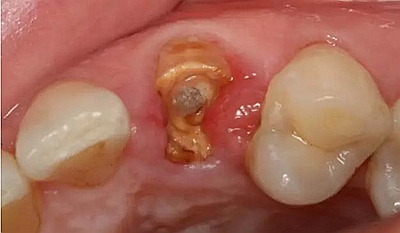

以下為術中照片。

內(nèi)斜切口,頸圈組織,改良垂直褥式縫合。